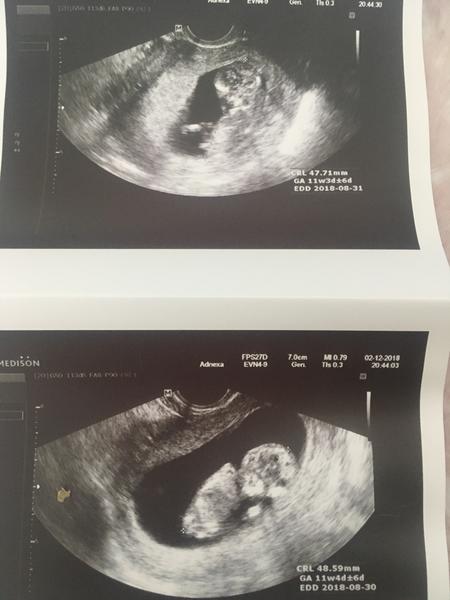

@natysnovec dekuju ❤️ Rostou jako z vody! Kdyz mi dr rekl, ze maji obe 5 cm tak se mi nechtelo verit :D